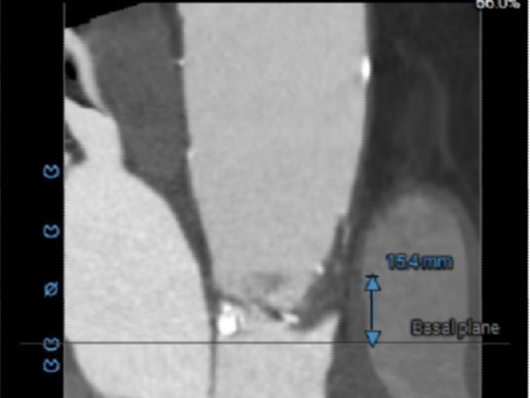

ANNULUS

2mm SUPRA ANNULUS